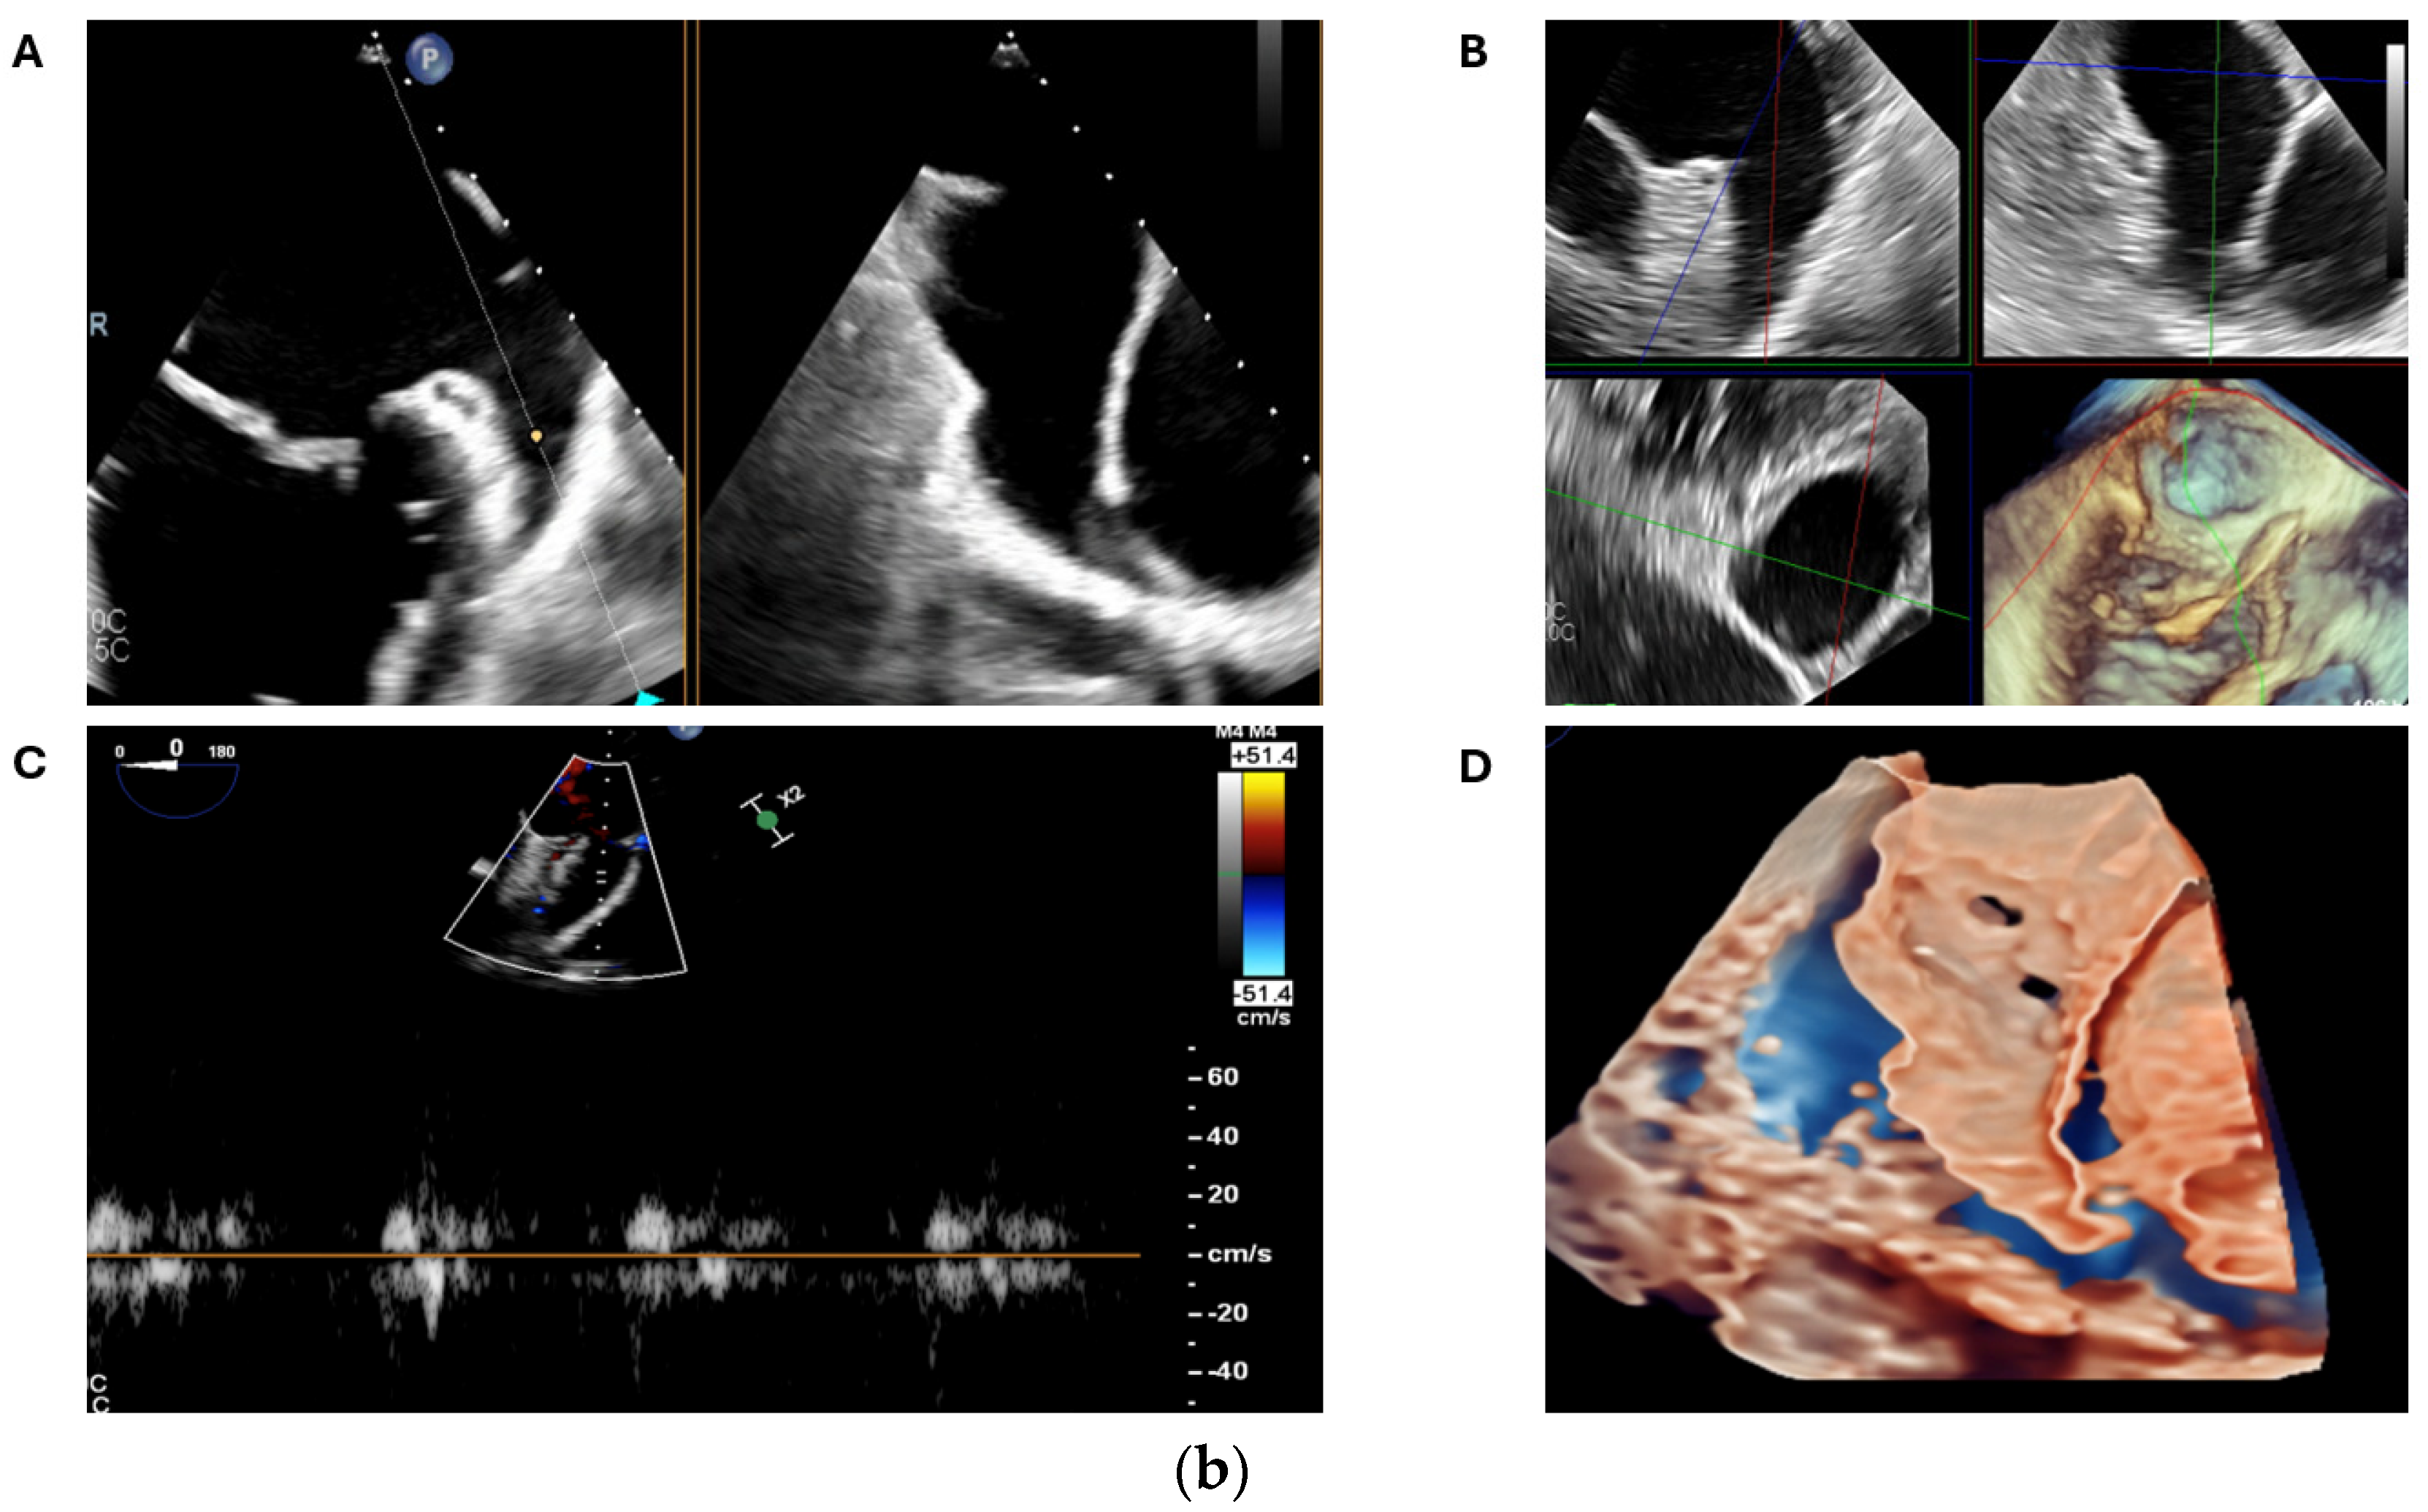

- Sun, A.; Ren, S.; Xiao, Y.; Chen, Y.; Wang, N.; Li, C.; Tan, X.; Pan, Y.; Sun, F.; Ren, W. Real-Time 3D Echocardiographic Transilluminated Imaging Combined with Artificially Intelligent Left Atrial Appendage Measurement for Atrial Fibrillation Interventional Procedures. Front. Physiol. 2022, 13, 1043551. [Google Scholar] [CrossRef]

- Okafor, J.; Rana, B.S. Importance of Echocardiography in Navigating Left Atrial Appendage Function, Thrombus Exclusion and Percutaneous Closure. Clin. Res. Cardiol. 2024, 1–3. [Google Scholar] [CrossRef]

- Ramchand, J.; Harb, S.C.; Miyasaka, R.; Kanj, M.; Saliba, W.; Jaber, W.A. Imaging for Percutaneous Left Atrial Appendage Closure: A Contemporary Review. Struct. Heart 2019, 3, 364–382. [Google Scholar] [CrossRef]

- Nucifora, G.; Faletra, F.F.; Regoli, F.; Pasotti, E.; Pedrazzini, G.; Moccetti, T.; Auricchio, A. Evaluation of the Left Atrial Appendage with Real-Time 3-Dimensional Transesophageal Echocardiography Implications for Catheter-Based Left Atrial Appendage Closure. Circ. Cardiovasc. Imaging 2011, 4, 514–523. [Google Scholar] [CrossRef] [PubMed]

- Yosefy, C.; Laish-Farkash, A.; Azhibekov, Y.; Khalameizer, V.; Brodkin, B.; Katz, A. A New Method for Direct Three-Dimensional Measurement of Left Atrial Appendage Dimensions during Transesophageal Echocardiography. Echocardiography 2016, 33, 69–76. [Google Scholar] [CrossRef] [PubMed]

- Vainrib, A.F.; Harb, S.C.; Jaber, W.; Benenstein, R.J.; Aizer, A.; Chinitz, L.A.; Saric, M. Left Atrial Appendage Occlusion/Exclusion: Procedural Image Guidance with Transesophageal Echocardiography. J. Am. Soc. Echocardiogr. 2018, 31, 454–474. [Google Scholar] [CrossRef] [PubMed]